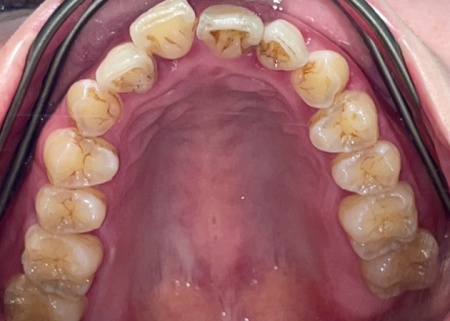

30代女性 出っ歯と乱れた噛み合わせによる口の閉じにくさをマウスピース矯正治療で改善した症例

拝見したところ、上顎前歯が前方に突き出ている出っ歯の状態でした。

出っ歯のため、見た目に影響が出ているだけでなく噛み合わせも乱れ、口が閉じにくくなっている状態です。

以上のことから、審美性と噛み合わせを改善する治療が必要であると診断しました。